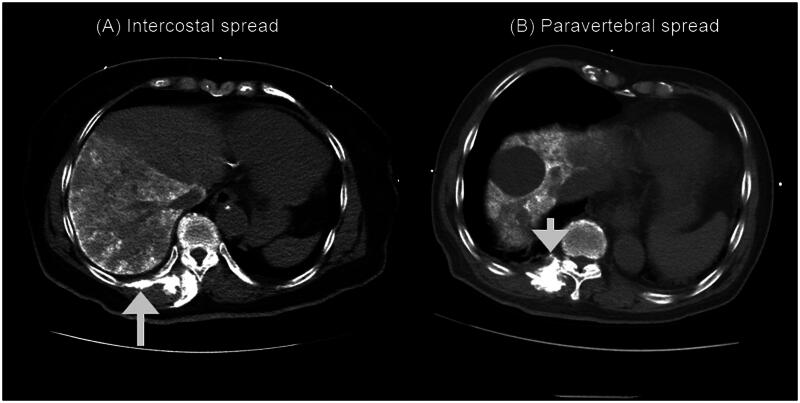

Results: The ESPB consistently spread cranio-caudally to the dorsal erector spinae muscle in all patients, with a median (IQR) spread of 9 (8-11) vertebral levels, and to the intercostal space with a median (IQR) spread of 4 (3-6) vertebral levels. Paravertebral spread occurred in 90% of patients (27 out of 30) with a median (IQR) spread of 3 (2-5) vertebral levels, while epidural spread was observed in 36.7% of patients (11 out of 30) with a median (IQR) spread of 0 (0-2) vertebral levels. Cranio-caudal spread negatively correlated with back muscle thickness (r= -0.4; p = 0.035), and females exhibited significantly more intercostal spread levels than males (5.8 ± 1.0 vs. 4.3 ± 1.6 levels in females and males, respectively; p = 0.021). However, no significant difference was found in pain intensity and morphine consumption between the two study groups.